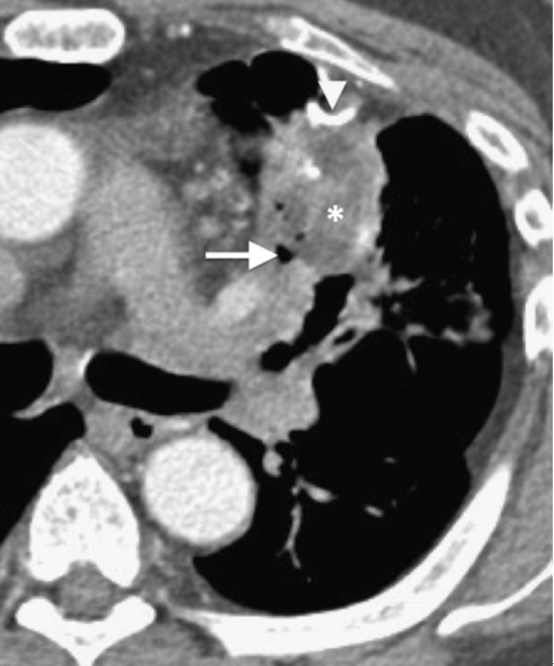

4. 侵袭性肺曲菌病主要发生在免疫功能严重受损的患者,常伴中性粒细胞减少。局部肺动脉被菌丝堵塞,曲霉菌对血管有特殊的亲和力,侵犯血管导致血栓形成,造成小的梗死灶,梗死灶周围的出血和渗出形成CT上边缘模糊的磨玻璃影,称“晕征”。约1~3周后,随着中性粒细胞水平恢复正常,感染区会形成空洞,出现“空气新月征”(图6),此征象是由梗死的肺组织回缩牵拉空洞壁造成的,也被认为是预后良好的表现。

图 6 急性白血病骨髓移植术后患者,中性粒细胞减少。(a)左肺上叶局部实变(*),伴周围磨玻璃样晕环。(b)恢复期可见“空气新月征”(箭头)。(c)残留的瘢痕和小空洞(箭头)。痰培养证实为烟曲菌感染。